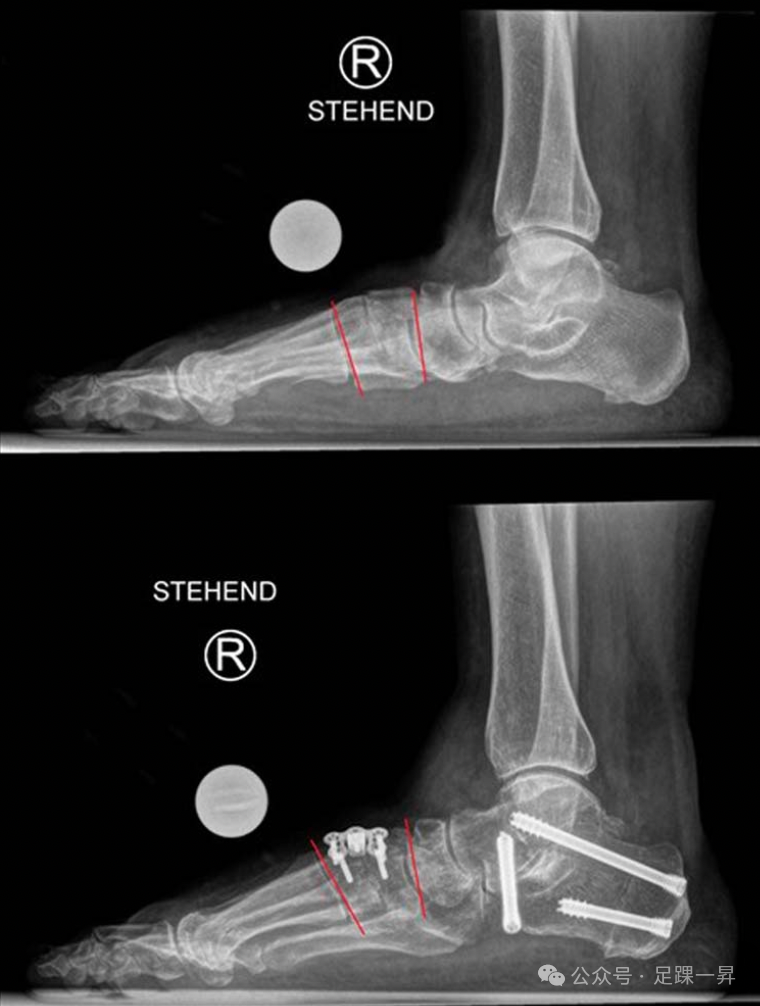

高弓足顾名思义指的是侧面观足弓高企,在行走或者负重过程中过程失去弹性,不能相对变平,从而不能完成正常站立和行走功能。